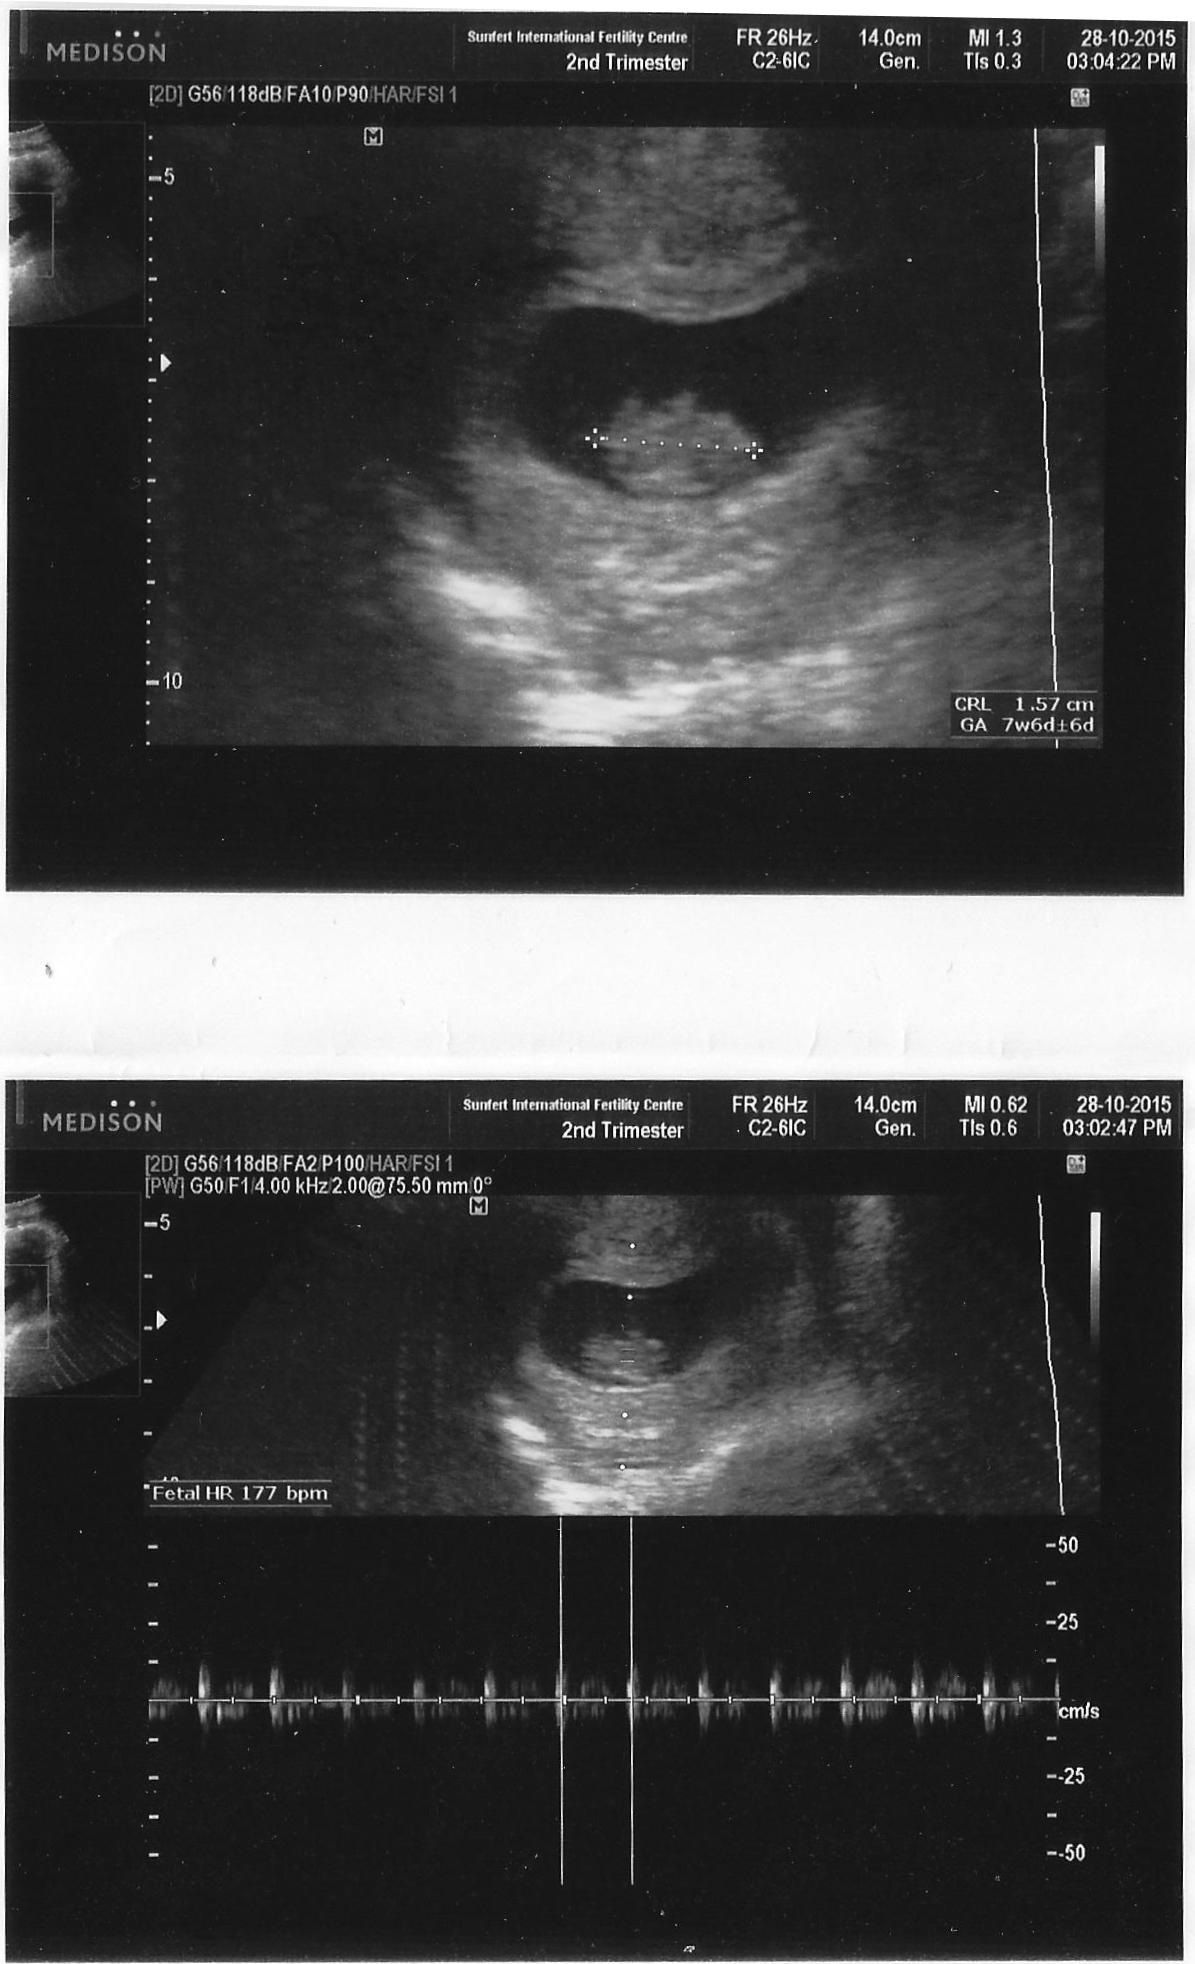

8 weeks ultrasound

Our Lil’ BB has grown so much! :’D Can you see the little limbs on top? Sweet. BB’s heartbeat is more visible now. *loves* Measuring only 1.57cm. Still as small as ever. A little bean with little limbs.